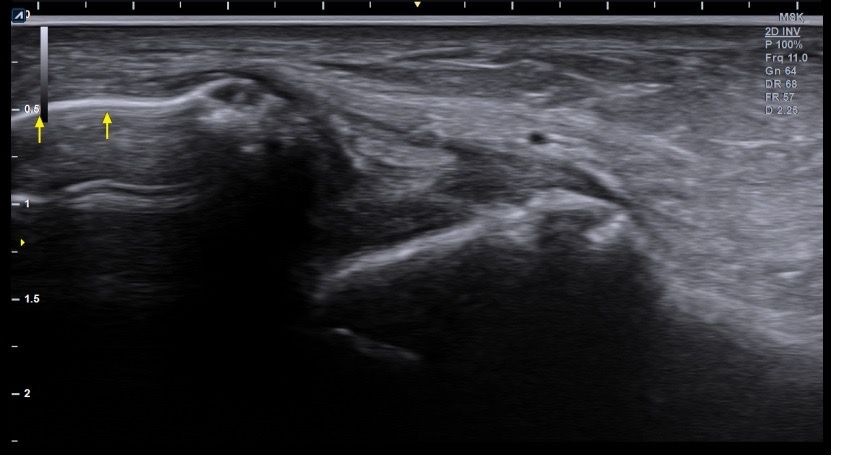

복숭아뼈 미세골절 초음파 사진 관련 질문

발목 접지른 후 치료받는 중인데요 복숭아뼈 미세골절이라고 하셨네요 3월 1일 다친뒤네 3월7일 병원방문후에 위에 초음파랑 엑스레이 촬영했고요 그뒤 반깁스 중입니다. 위에 엑스레이 상에선 안나오는데 초음파 사진에선 미세골절이 맞을까요? 골절이 경미한 수준인지 아니면 중한 건지 궁금합니다 그리고 다음주에 병원 방문 후 초음파 또 촬영하기로 했는데 그때 반깁스도 풀 수 있을까요??

• 3번 째 사진

약간의미세골절을 의심할 수 있는 상태로 보이는데요, 우선은 치료계획대로 진행하시는 것이 좋겠습니다.

발목의 복숭아뼈에 미세골절이 의심되는 경우, 엑스레이에서는 미세골절이 잘 보이지 않을 수 있습니다. 엑스레이는 큰 골절을 잘 확인하지만, 미세한 골절이나 염증 반응은 잘 나타나지 않기 때문이죠. 초음파는 조직의 변화를 보다 민감하게 감지할 수 있기 때문에, 미세골절을 발견하는 데 도움을 줄 수 있습니다. 초음파에서 미세골절이 확인되었다면, 이는 경미한 골절일 가능성이 높아요. 하지만 골절의 정확한 상태나 치유 과정을 판단하려면 정밀 검사가 필요하죠